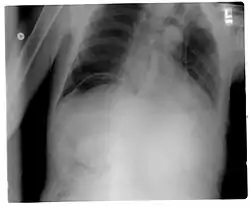

Un pneumopéritoine de faible volume est le plus souvent asymptomatique. Il est avant tout suspecté dans un contexte clinique. La radiographie (abdomen sans préparation (ASP) et/ou cliché debout de face, centré sur les coupoles diaphragmatiques) permet généralement de faire le diagnostic, le pneumopéritoine apparaissant comme un croissant radio transparent sous-diaphragmatique, uni ou bilatéral et de taille variable[1]. Cependant, un pneumopéritoine de faible abondance peut facilement passer inaperçu a la radiographie. C'est pourquoi la tomodensitométrie (ou scanner abdominal) est aujourd'hui considérée comme l'examen de référence pour son diagnostic[2]. La tomodensitométrie permet de rendre visible des volumes aussi faibles que 5 cm3 d'air ou de gaz.